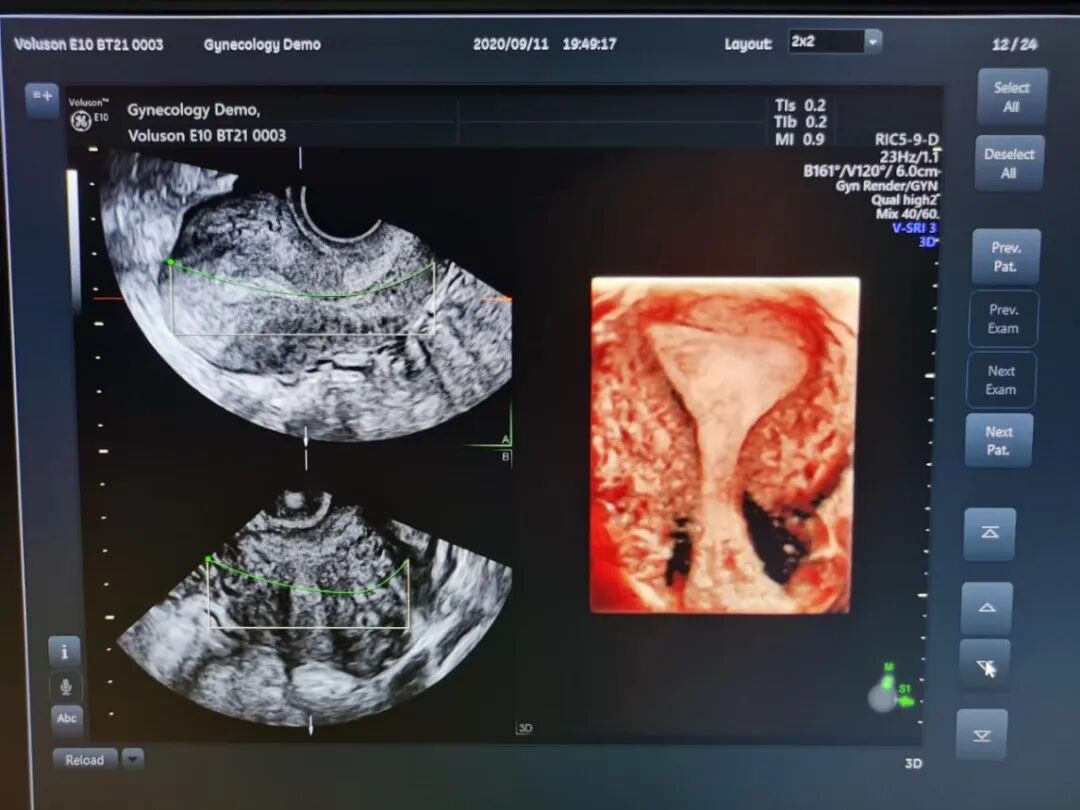

五、妇科疾病领域

更精准的图像能够对子宫畸形及宫腔病变、输卵管、卵巢、卵泡等进行全面评估;盆底三维四维超声有着多平面成像的优势,通过容积数据采集获得更清晰的图像,为临床诊断提供更丰富、有效的信息;妇科肿瘤方面,“煊流技术”提高了微小血管的敏感性有助于肿瘤良恶性的鉴别诊断。